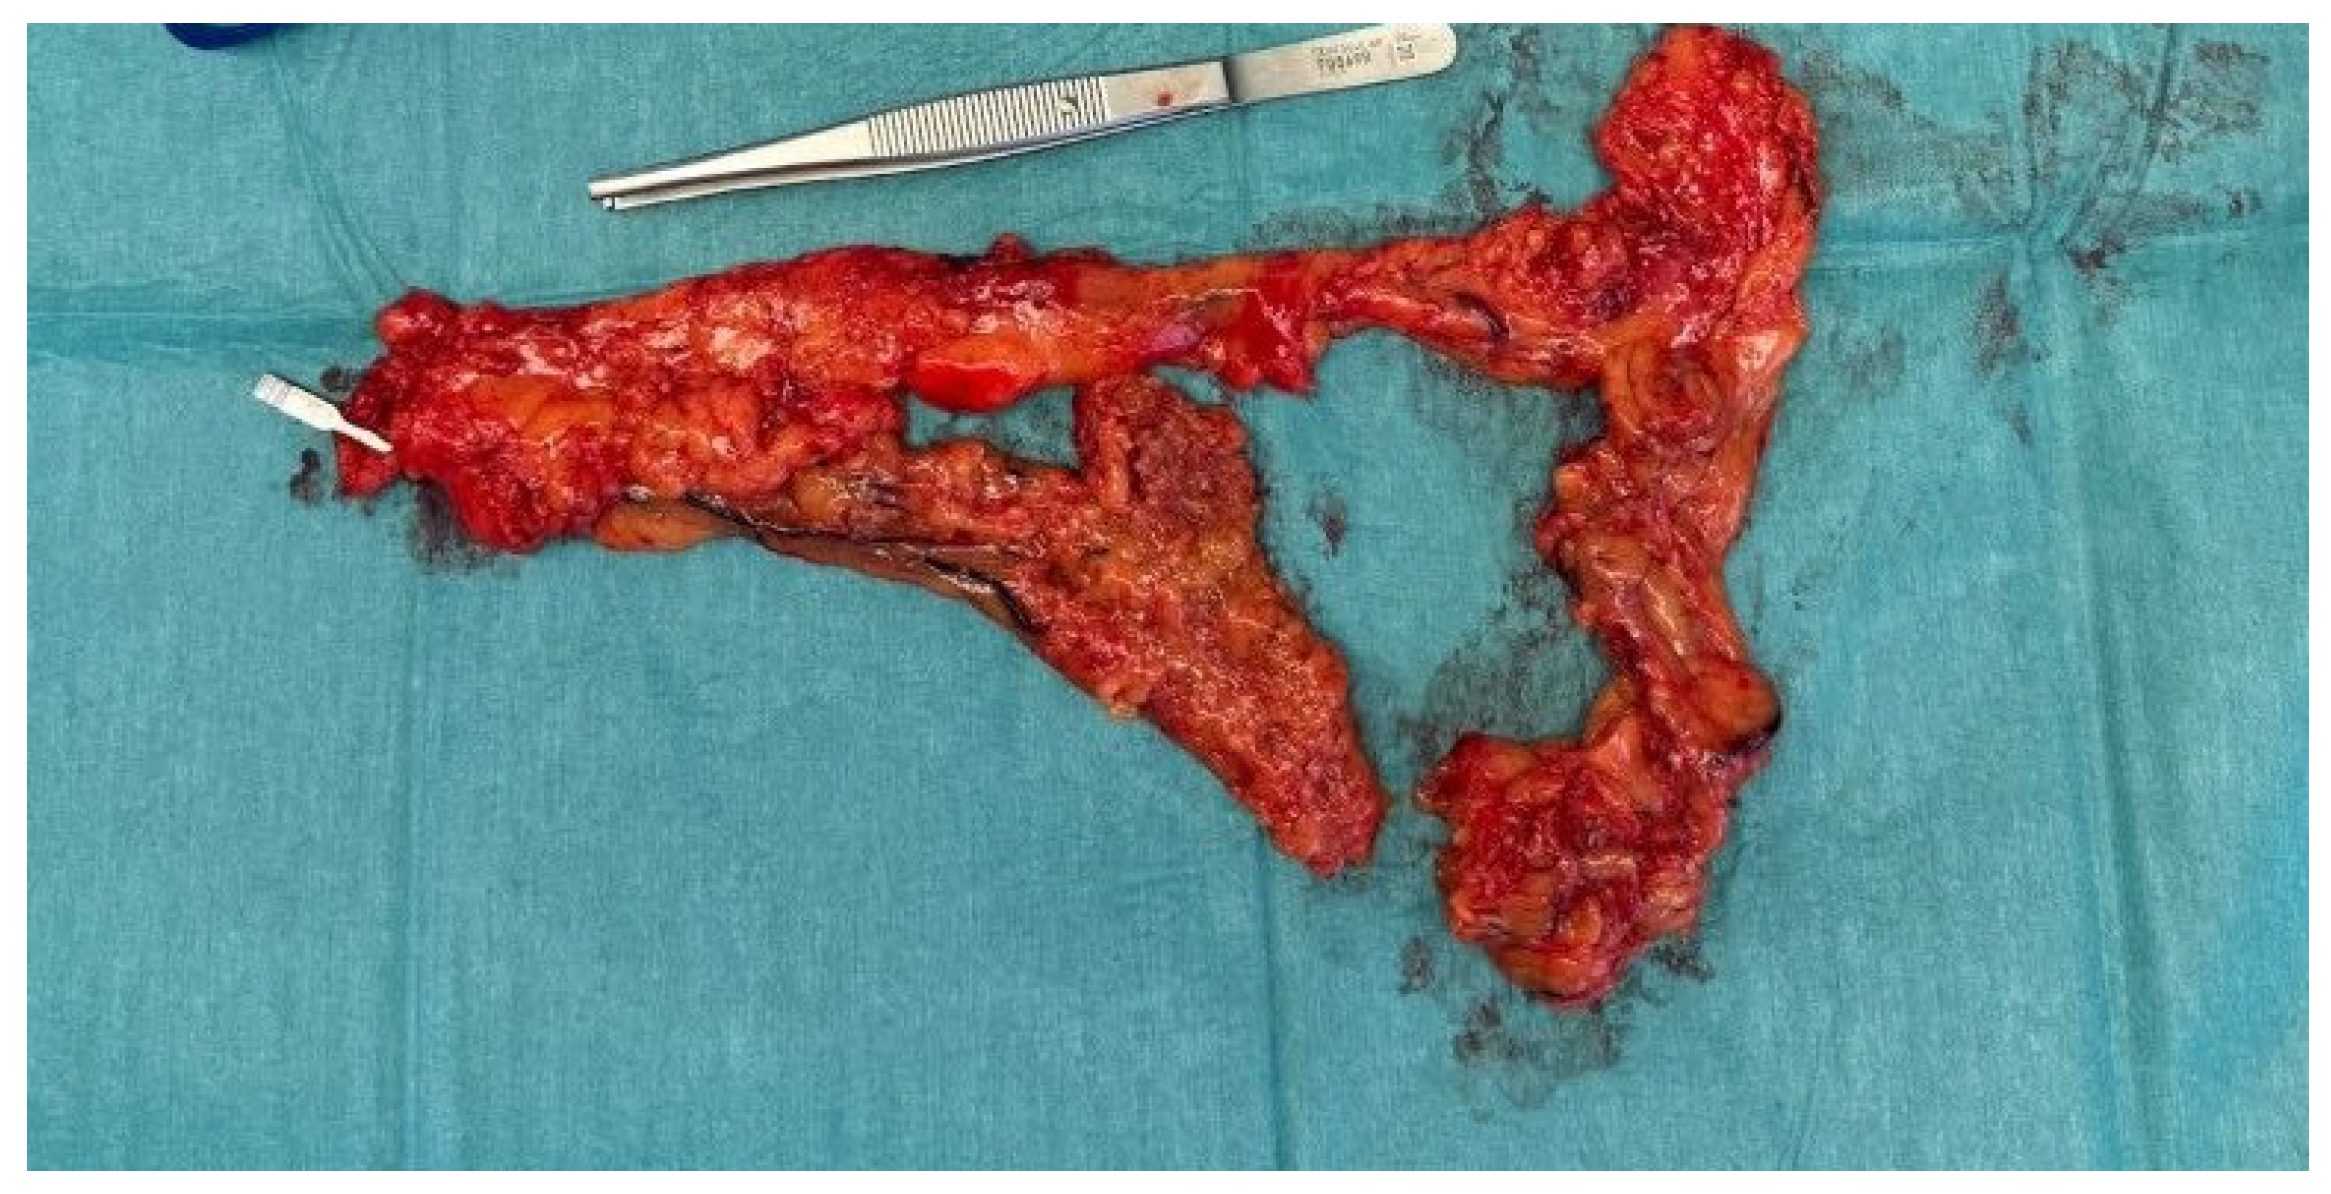

2. Case Report